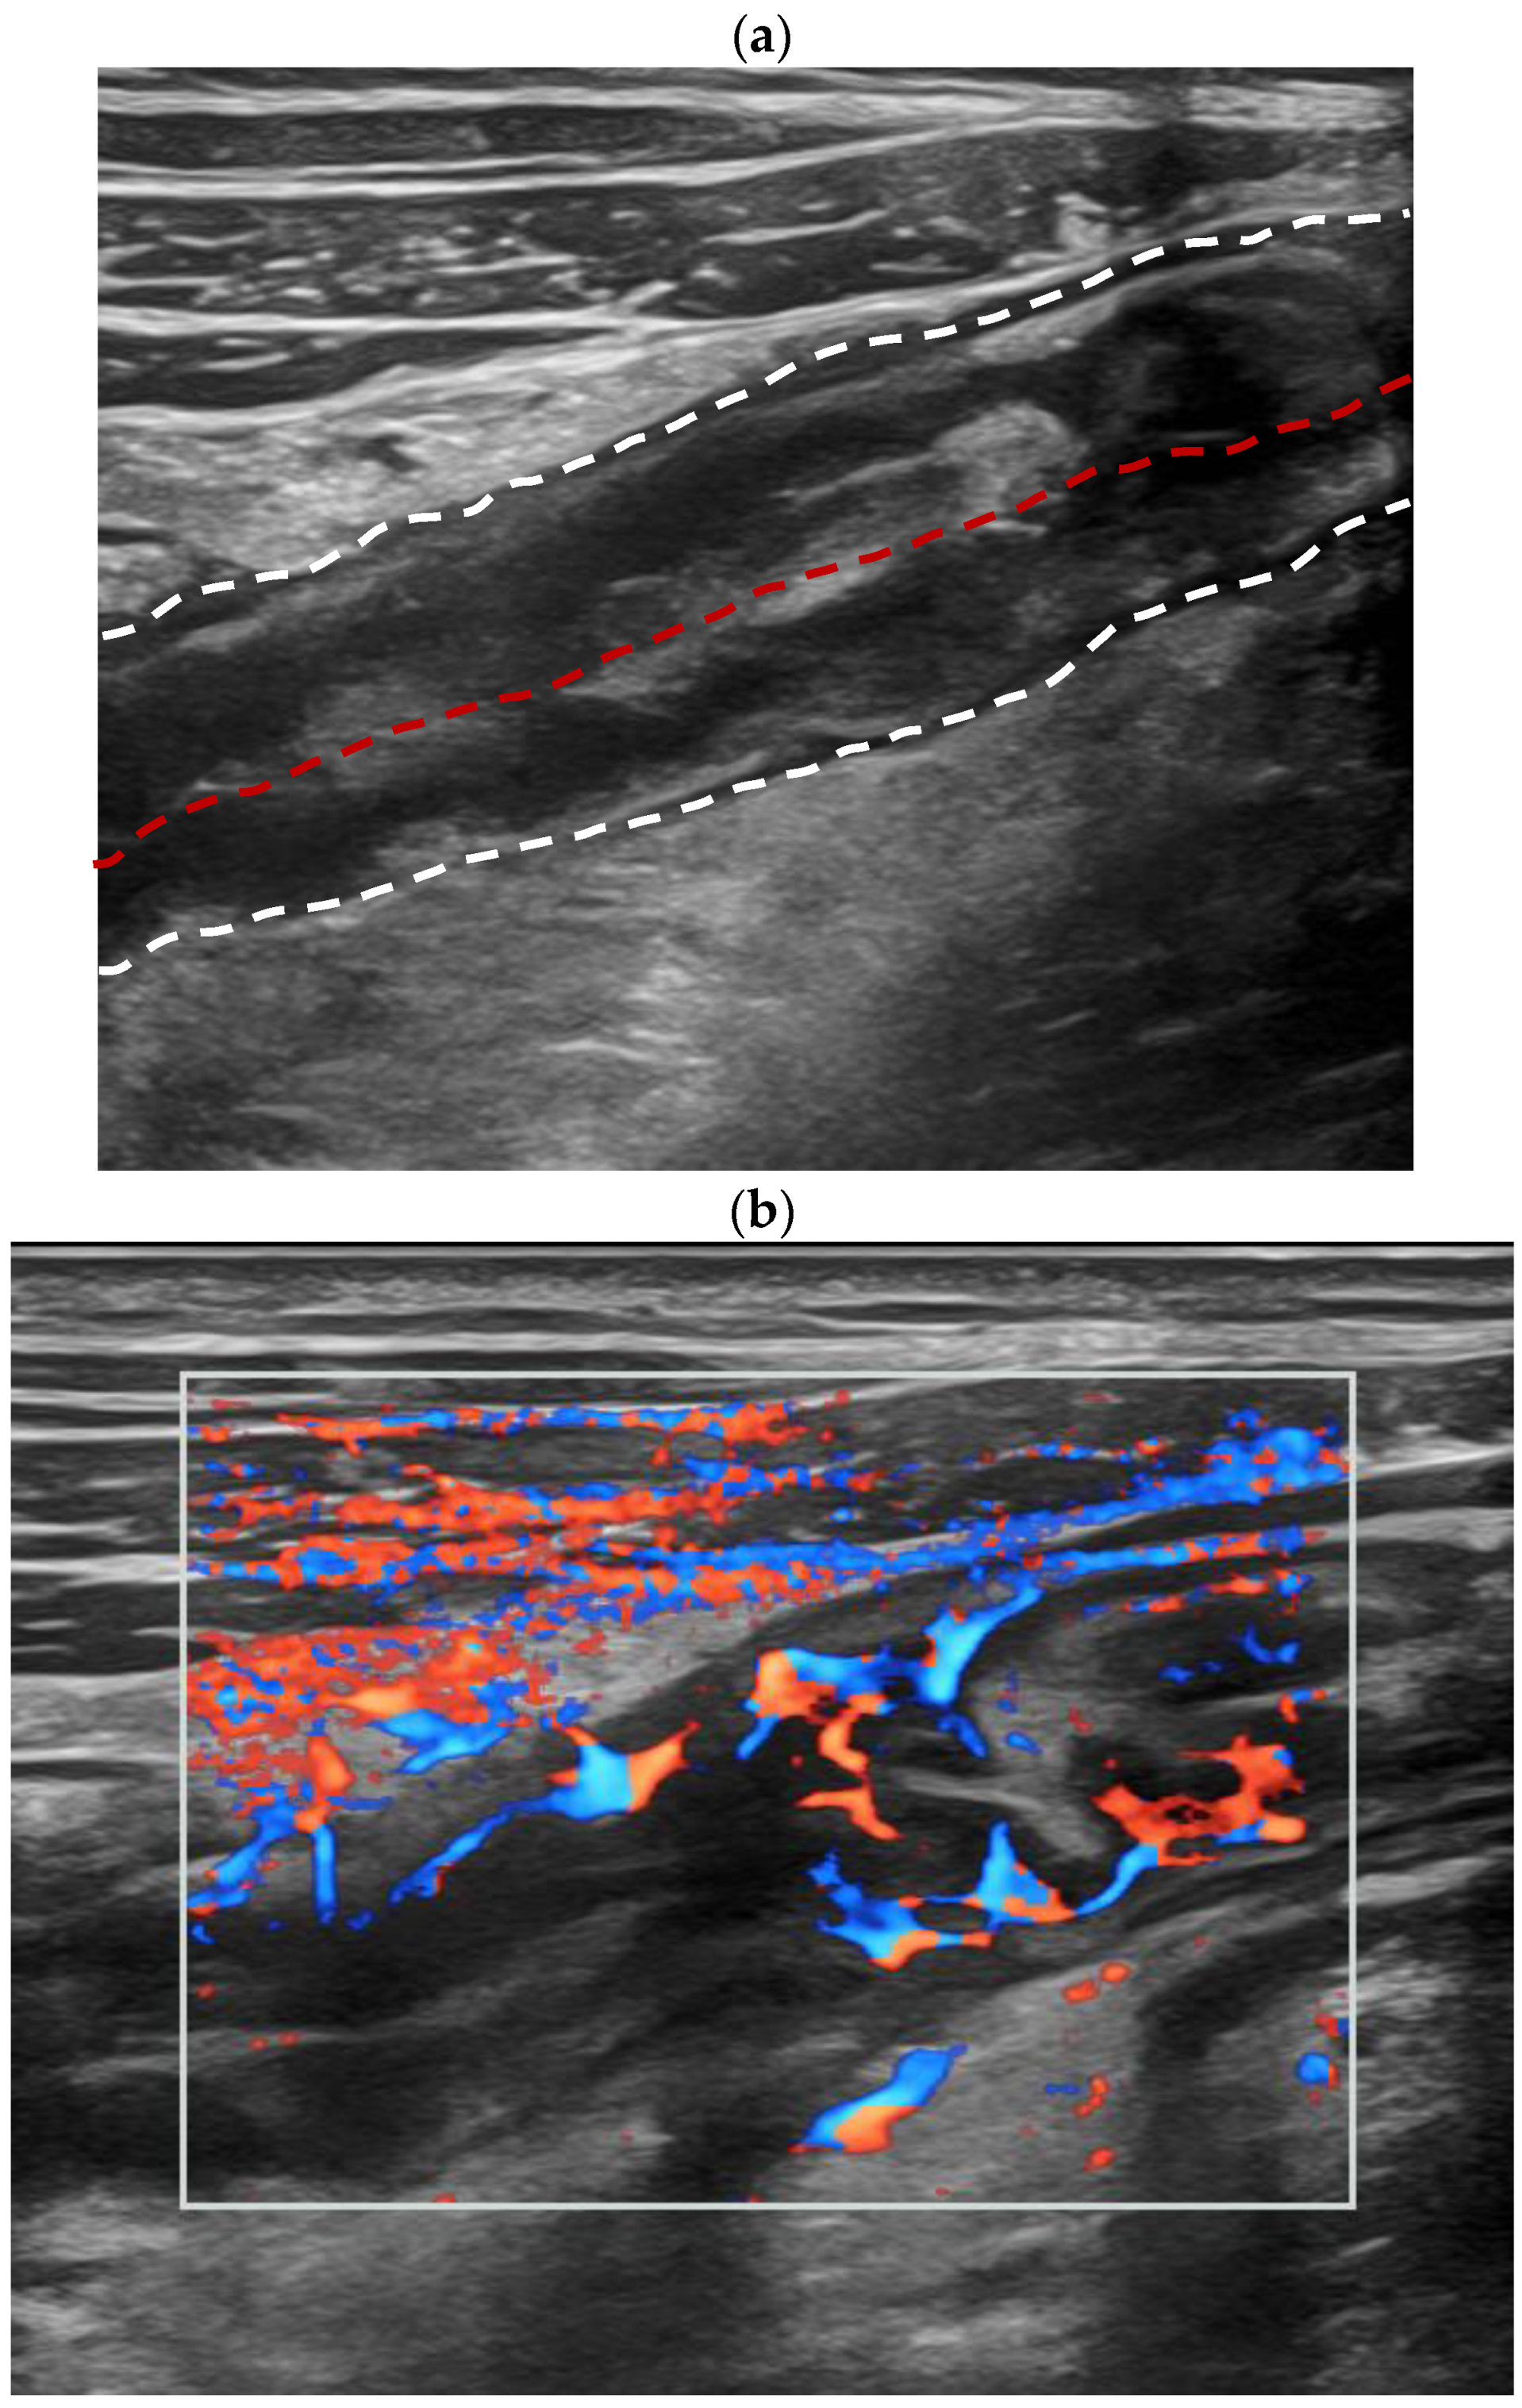

3.2. Intestinal Ultrasound Features

| Color Doppler signal | <0.001 * | ||

| Limberg 0 | 0 | 6 (46.1%) | |

| Limberg I | 5 (12.8%) | 3 (23.1%) | |

| Limberg II | 22 (56.4%) | 4 (30.8%) | |

| Limberg III | 7 (18.0%) | 0 | |

| Limberg IV | 5 (12.8%) | 0 | |